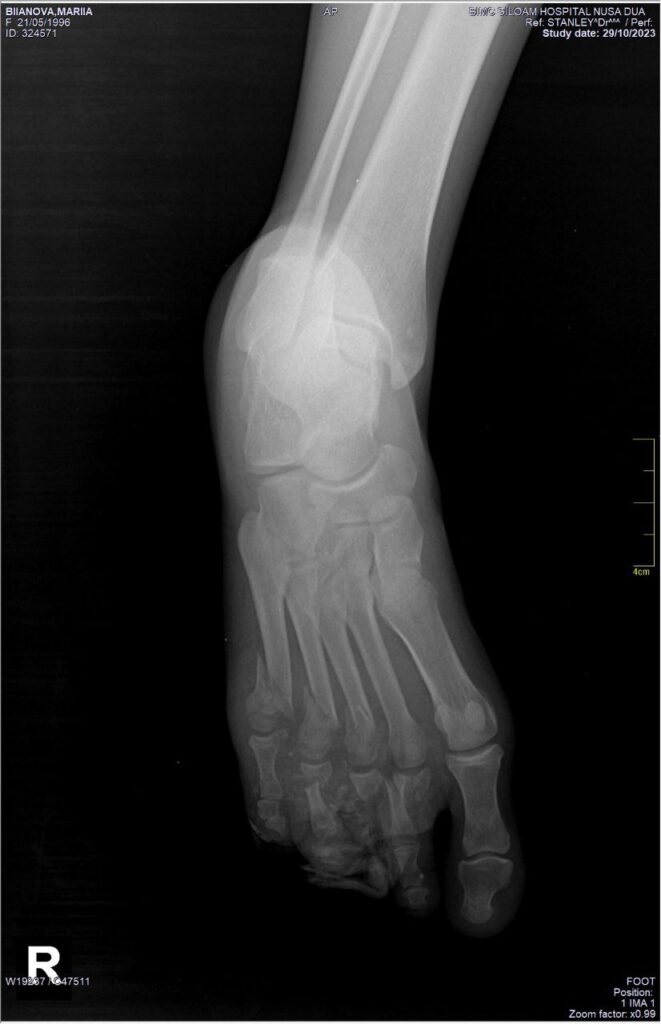

But I do remember that evening. I was lying on the street, watching cars go through, and I was scared they would not notice me and would just run over me. My body was paralysed by pain, so I couldn’t move. I even gave a command to my hand to move, but because I was paralysed by pain, I couldn’t. I thought I was completely smashed. But, thank God, only my right foot was crushed.

One Balinese guy named Roi took me from the street. I was bleeding and I could see my bones. I thought that this only happens in movies. We always think it happens only in movies or to someone else.